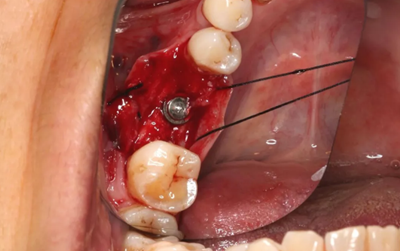

11、常規(guī)植入WEGO種植體一顆

牙槽嵴頂水平切口,翻瓣,牙槽嵴近中較遠(yuǎn)中豐滿。

(攝于2017年4月14日)